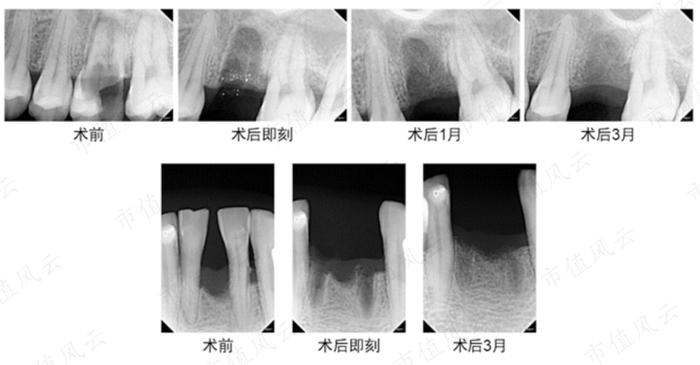

(矿化胶原骨修复产品的在口腔科的临床应用)